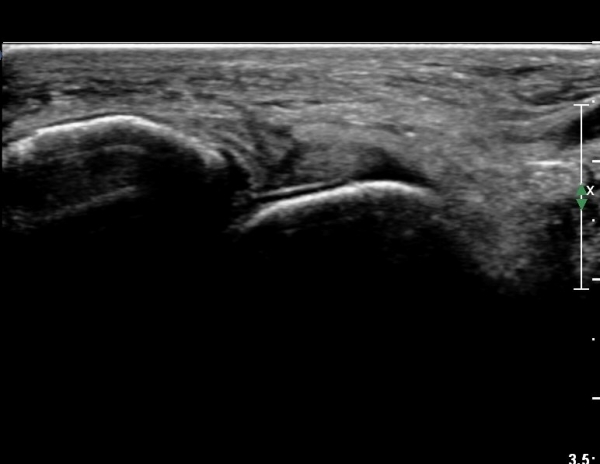

Àü°ÅºñÀδë Á¾´Ü¸é°Ë»ç¿¡¼­ Àü°ÅºñÀδëÀÇ ÆÄ¿­ÀÌ °üÂûµÈ´Ù(»çÁø 4, 5).